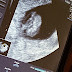

5w2d Ultrasound!!! I was only expecting to see a yolk sac but we could see a lil baby too!!! We go back next Monday to hear the heartbeat! ...